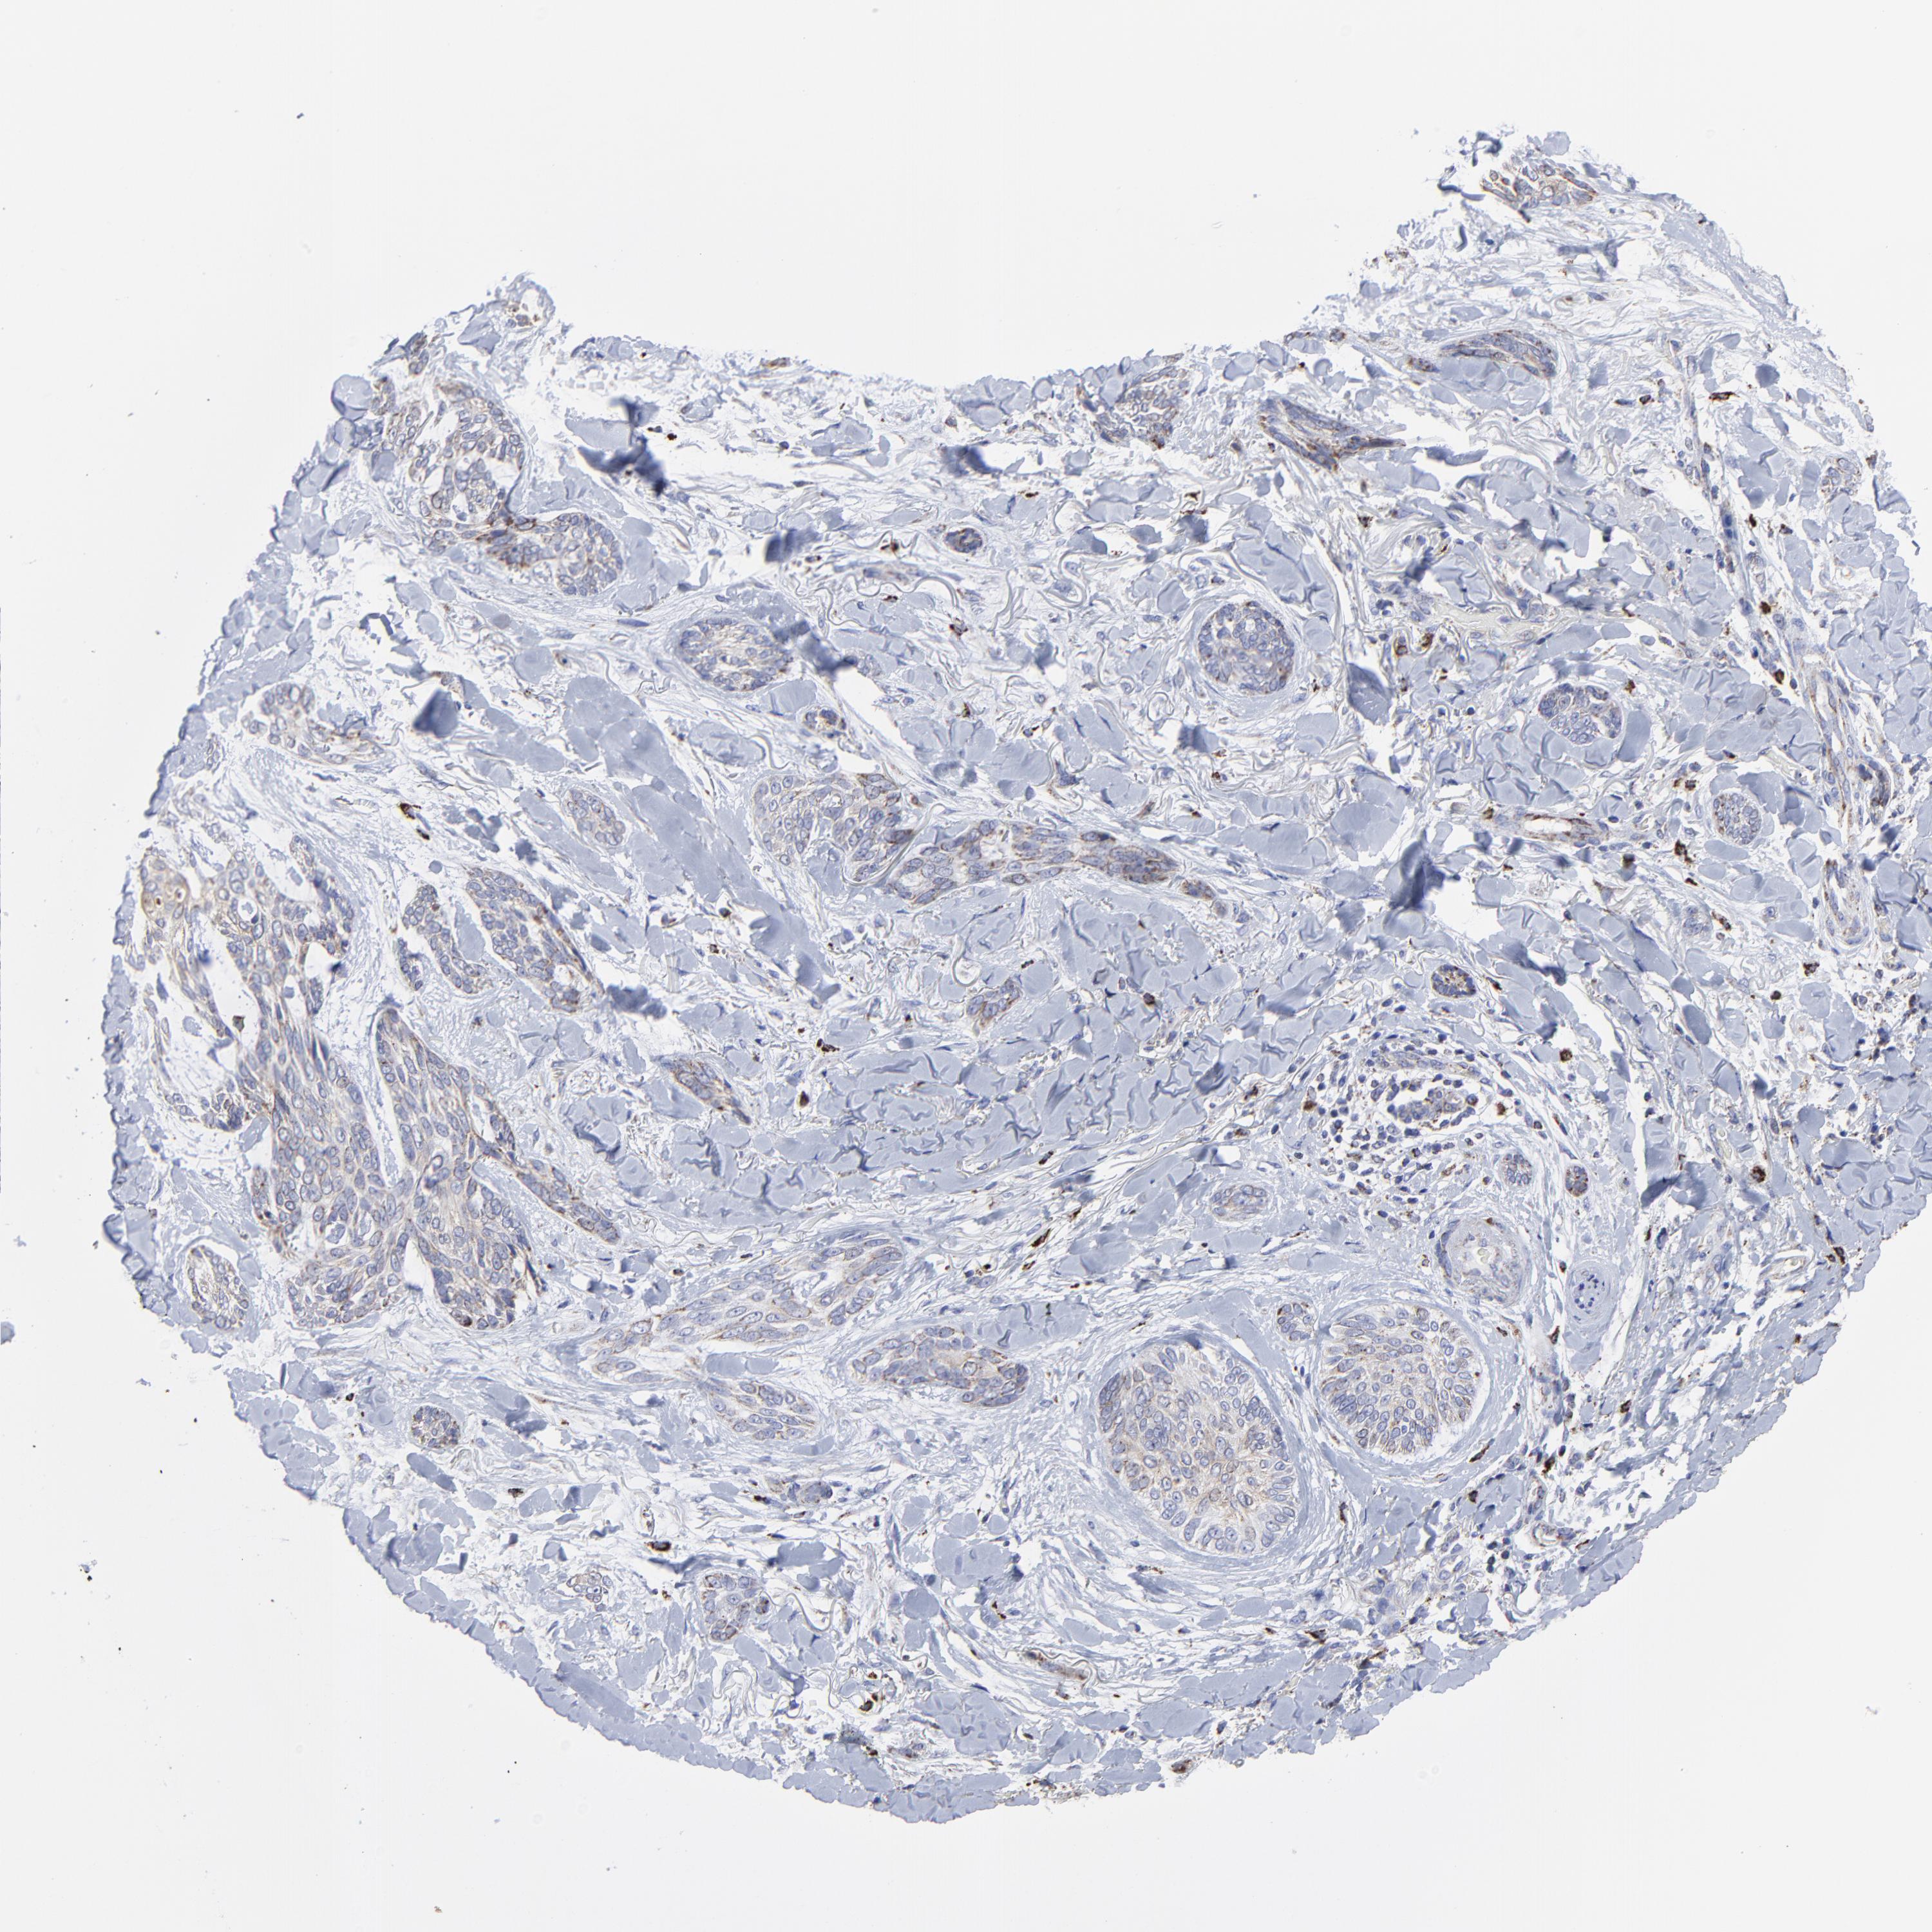

SKIN CANCER - Protein expressioni

A mouse-over function shows sample information and annotation data. Click on an image to view it in a full screen mode. Samples can be filtered based on level of antibody staining by selecting one or several of the following categories: high, medium, low and not detected. The assay and annotation is described here.

Antibody stainingi

Antibody staining in the annotated cell types in the current human tissue is reported as not detected, low, medium, or high, based on conventional immunohistochemistry profiling in selected tissues. This score is based on the combination of the staining intensity and fraction of stained cells.

Each image is clickable and will lead to virtual microscopy that enables deeper exploration of all samples and also displays staining intensity scores, fraction scores and subcellular localization as well as patient and tissue information for each sample.

Antibody CAB026191

Basal cell carcinoma